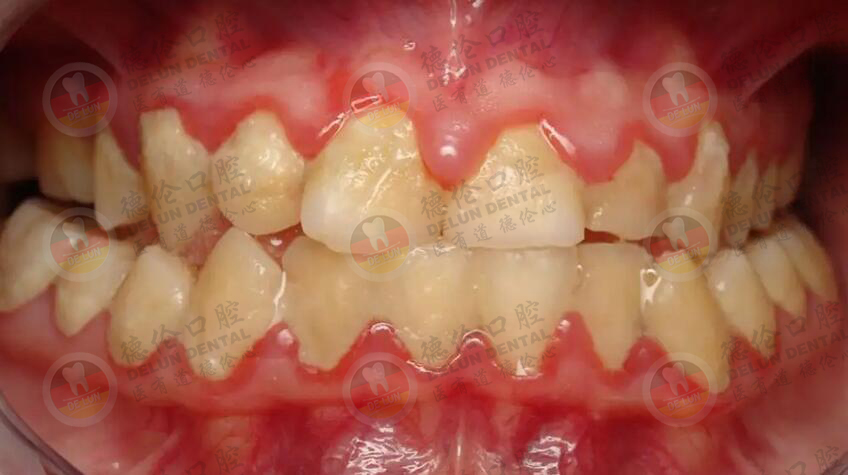

牙周炎早期症状包括口臭,牙齿动摇,牙龈红肿,刷牙流血,牙齿位置偏移,牙龈退缩,牙齿变长,此时须及早就诊,接受治疗。牙龈炎晚期,会有很多牙齿摇动厉害,齿龈发红肿胀,牙槽骨严重破坏,口腔卫生不良,口臭四溢,牙齿也产生移位和咬合错乱,这些症状也加重牙齿不舒适感,造成吃东西困难。领取免费口腔拍片,了解你的牙齿情况>>>